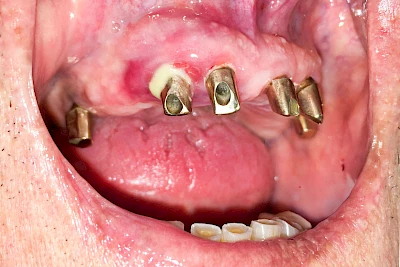

Bei Implantaten – also operativ eingebrachten künstlichen Zahnwurzeln – kann der Körper die Bakterien auch nicht so gut abwehren. Hier spricht man im Fall einer Entzündung von einer Peri-Implantitis, also einer Entzündung um das Implantat herum.